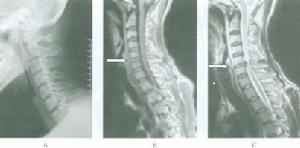

短頸畸形1.單純中下位頸椎融合引起的短頸畸形,早期常無神經症狀,不需特殊處理,但應注意避免頸椎過度活動,防止外傷,延緩頸椎退變的進程;對頸部外觀醜陋者,可行雙側頸部皮膚“Z”型成形術或雙側胸鎖乳突肌切斷術改善外觀。晚期因頸椎退變引起椎管狹窄出現脊髓受壓症狀者,可根據脊髓受壓部位行前路或後路減壓術。

2.上頸椎融合引起的短頸畸形,因可在早期出現神經症狀,應予以高度重視。對無神經症狀者,應隨訪觀察,防止頸部外傷,減少頸部活動或局部頸托固定,對出現神經症狀者,可採用相應的減壓和穩定手術。

3.短頸畸形創傷合引起脊髓損傷但不伴有骨性損傷者,應先採用非手術治療,如顱骨牽引或枕頜帶牽引,症狀消失後給予頭頸胸石膏固定;伴明顯骨折脫位者,則先採用顱骨牽引使之復位,然後根據神經症狀變化情況選擇治療方案。